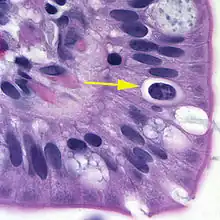

| Oocyst in epithelial cyst of mammalian host | |